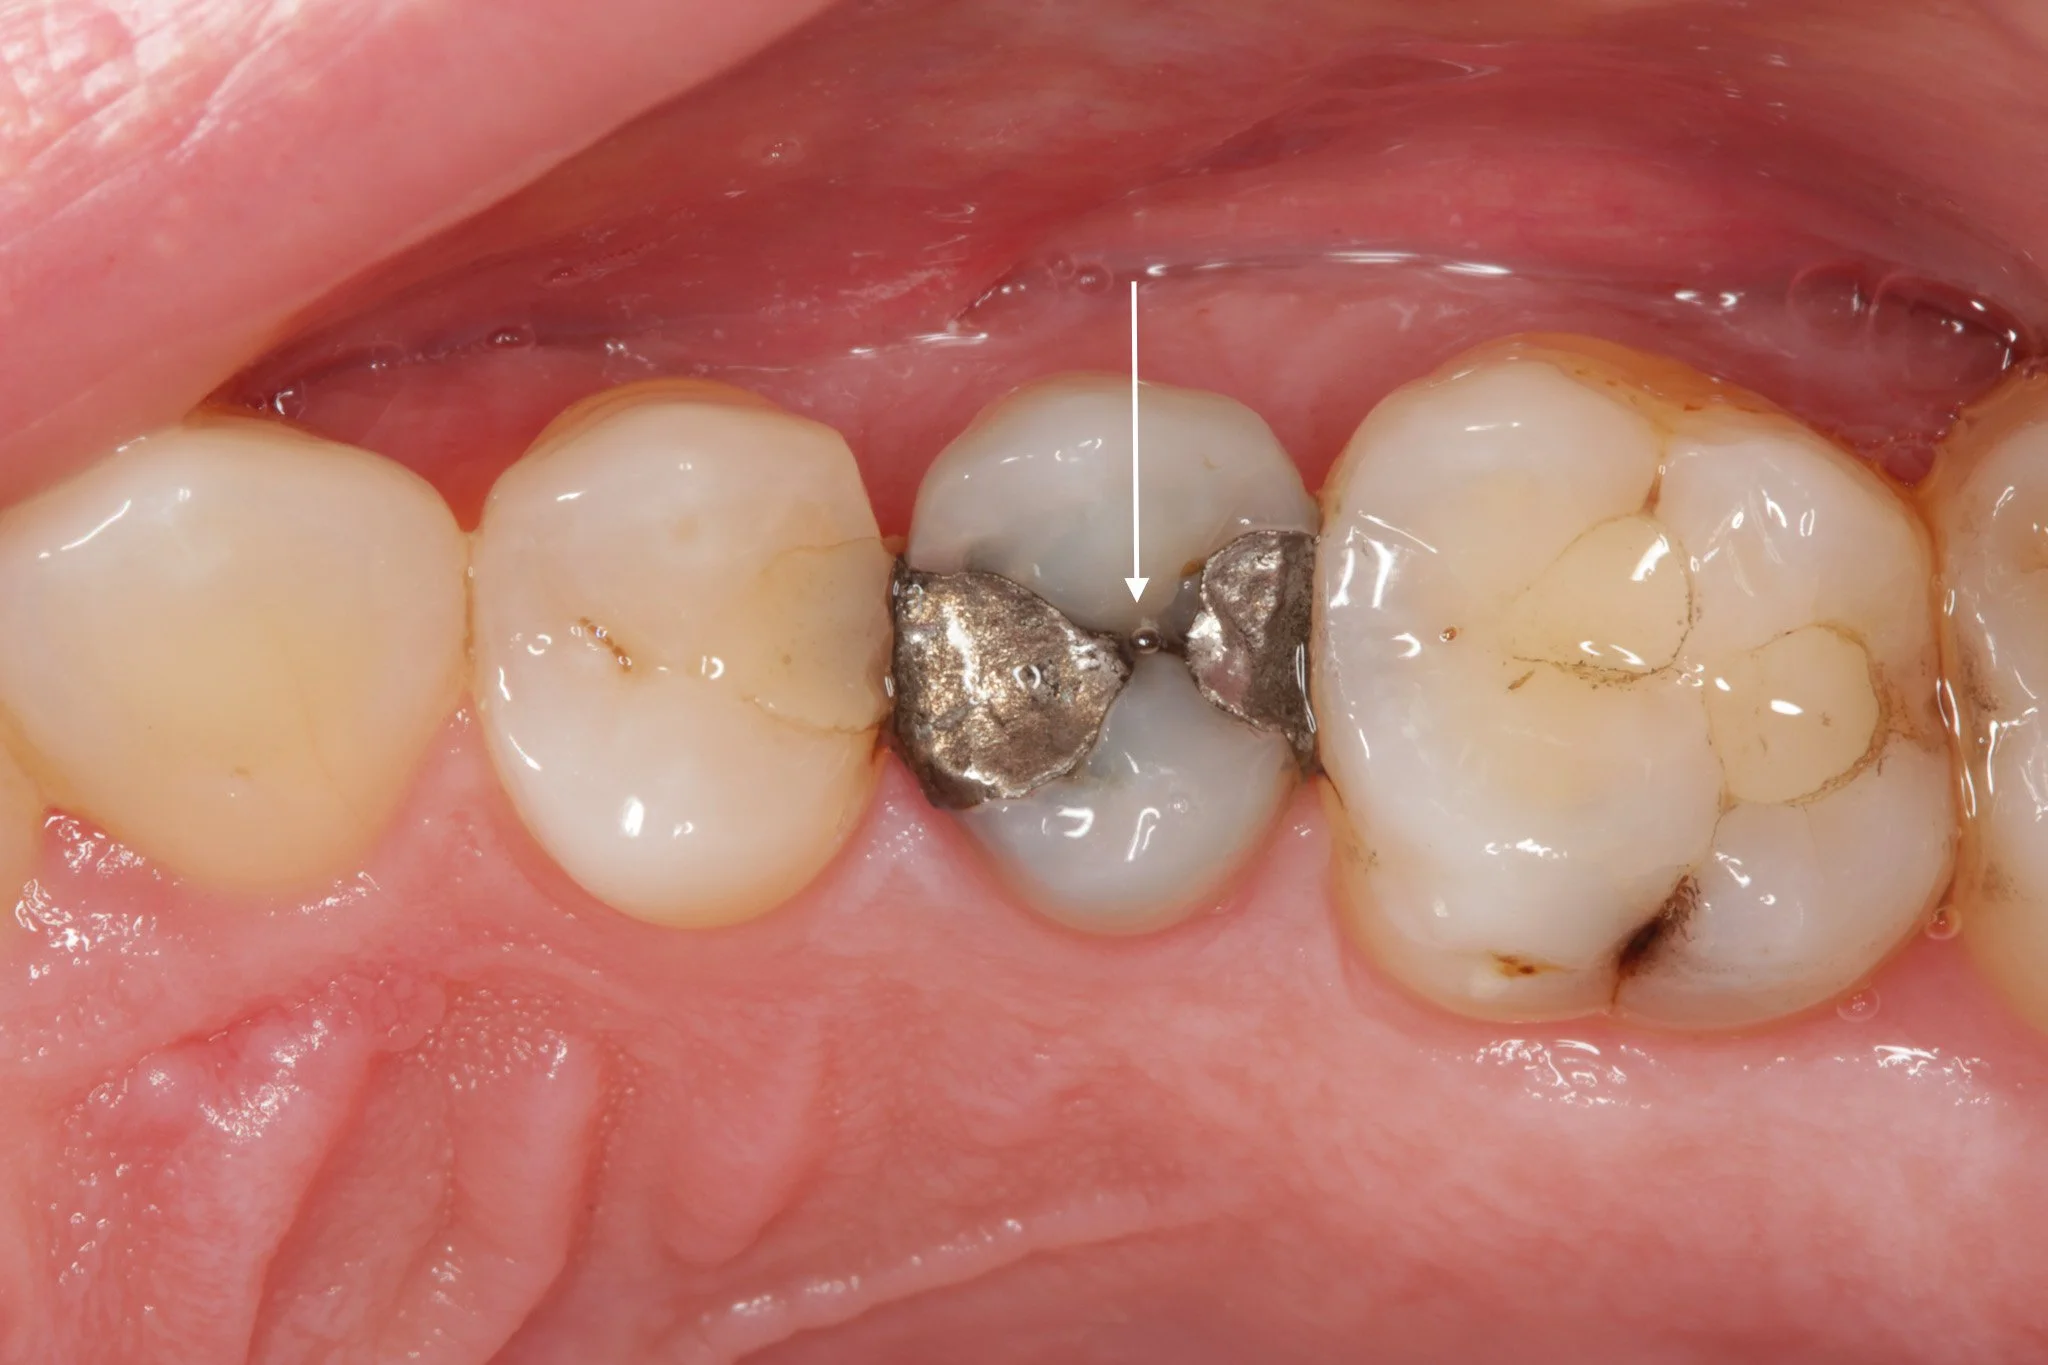

A tooth with decay

The decay is cleared away, leaving a hole

The hole is filled with a tooth-coloured composite resin